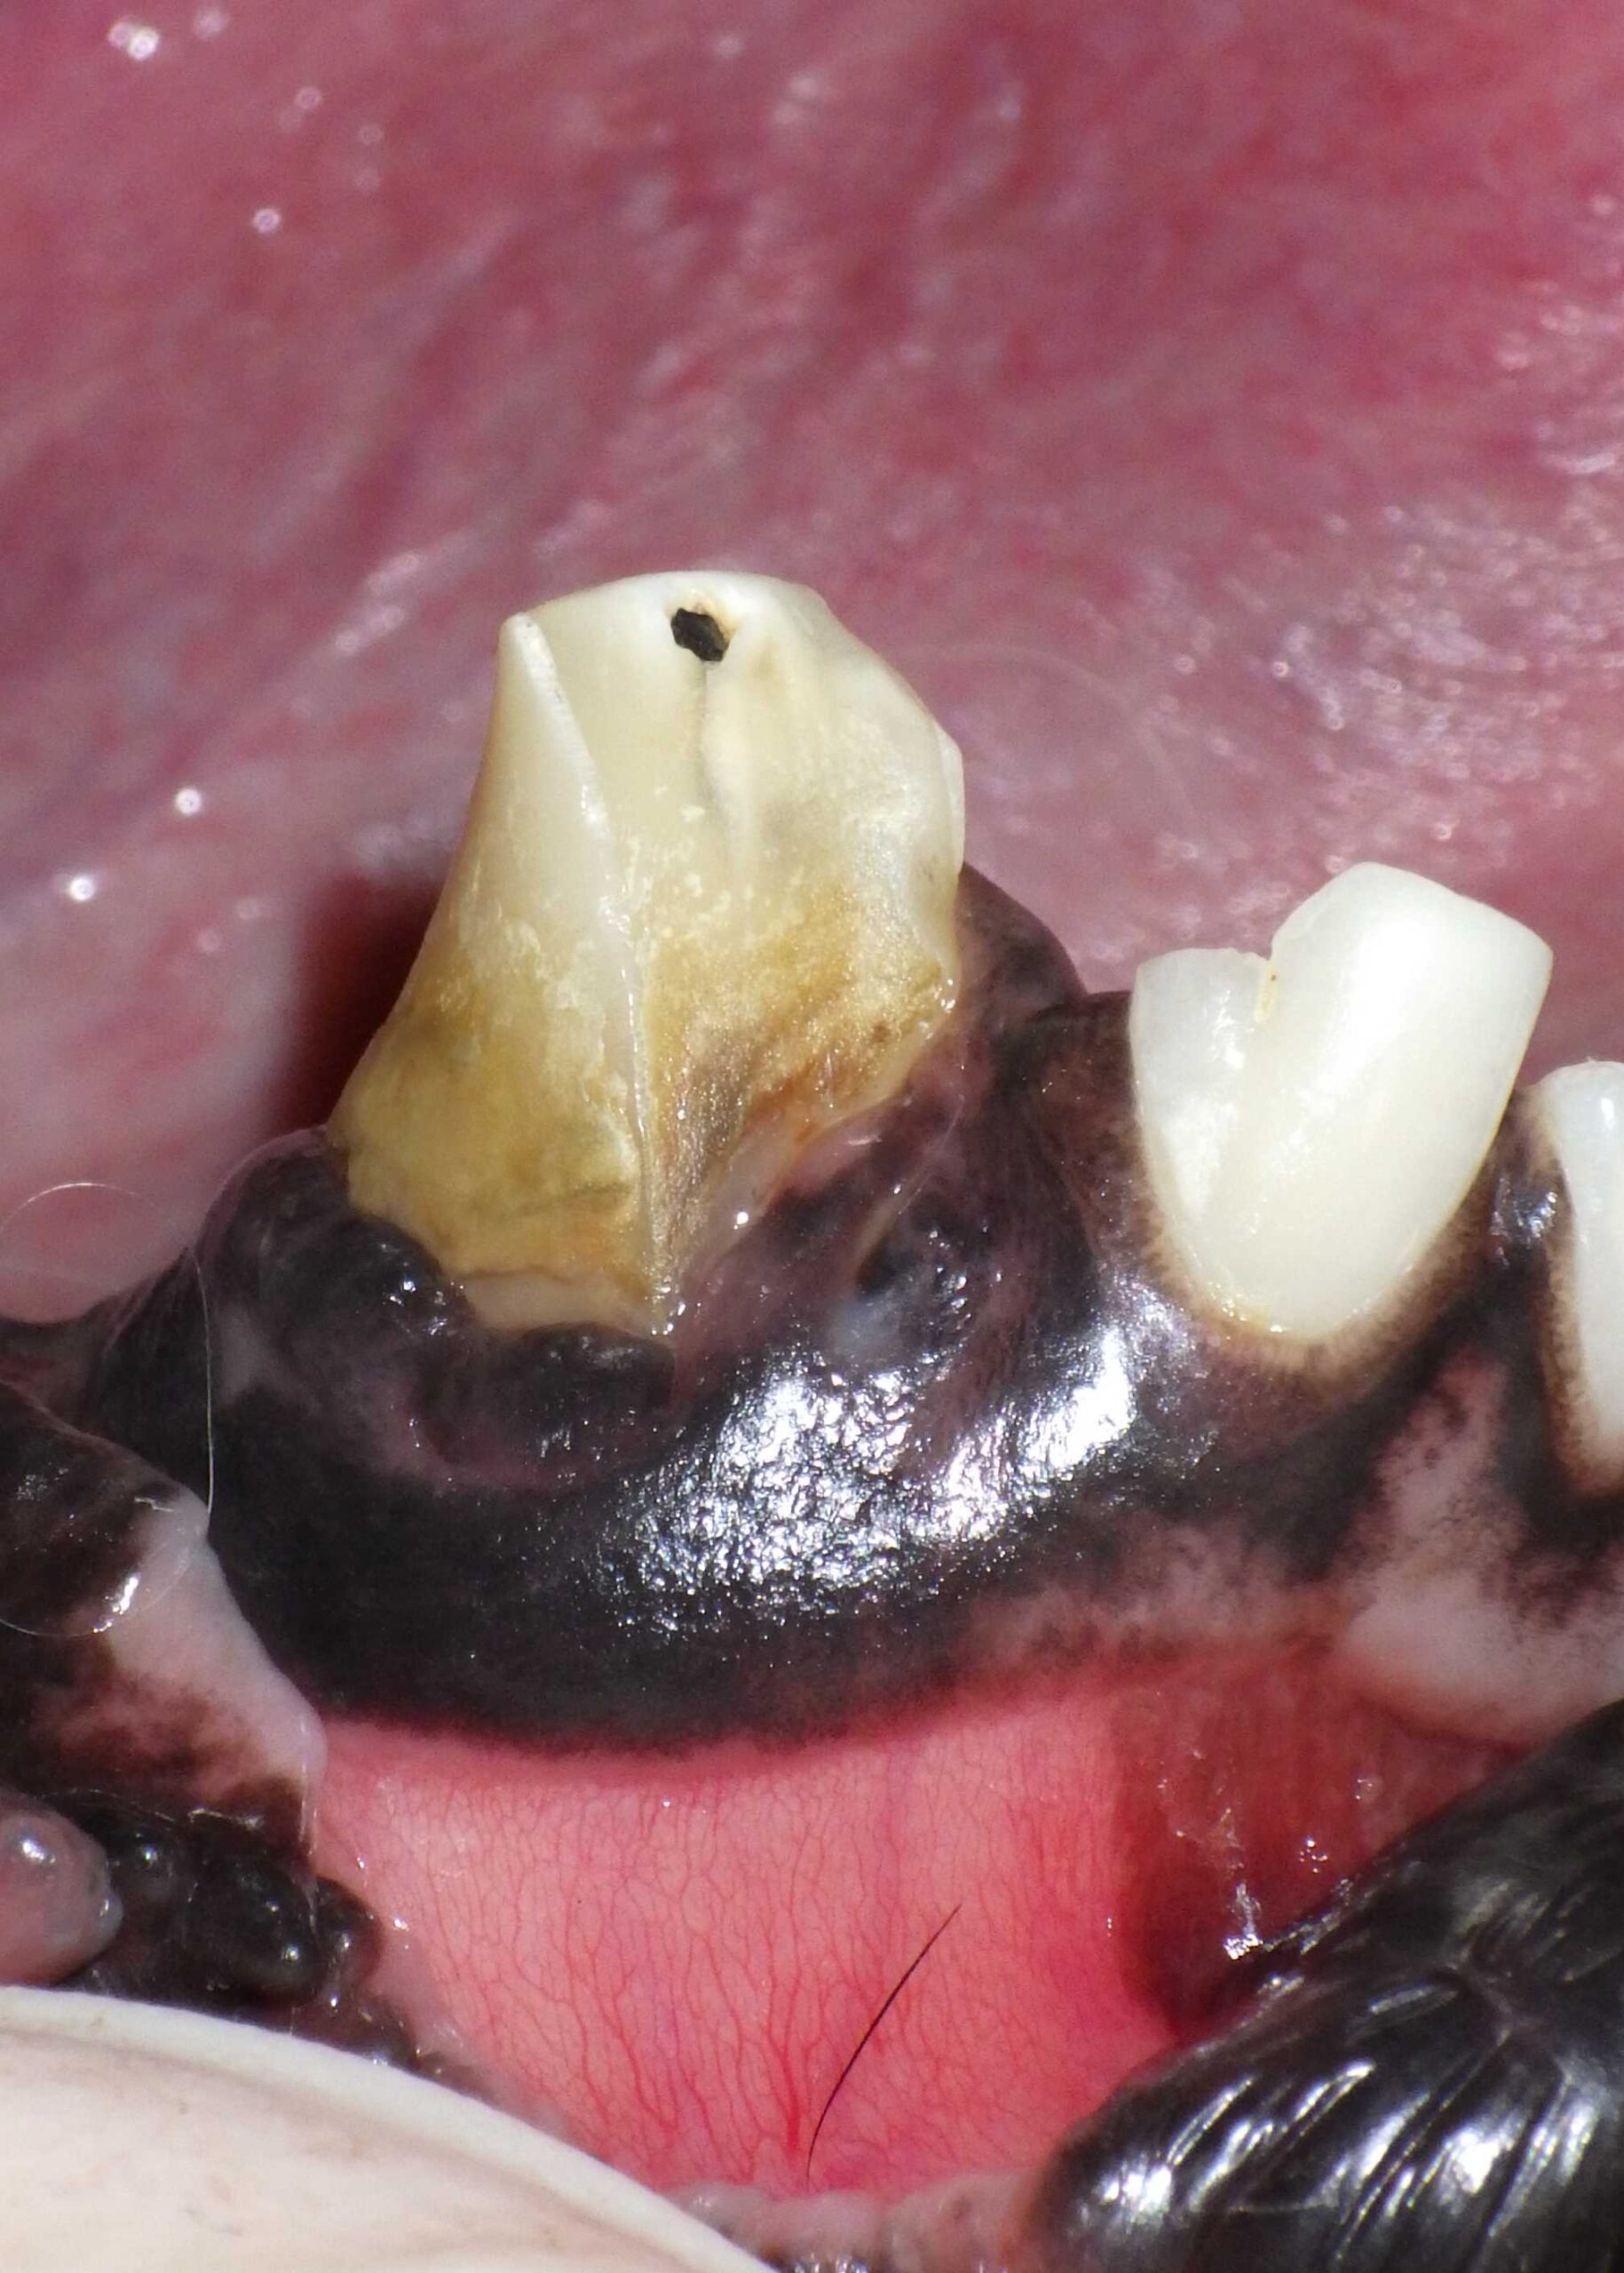

Fractured Tooth With Pulp Exposure

Often caused by chewing bones or trauma, this exposes the nerve and allows infection to enter.

Discolored Tooth

A tooth that looks grey, pink, or purple may be dead or inflamed inside—even if the outer surface appears fine.